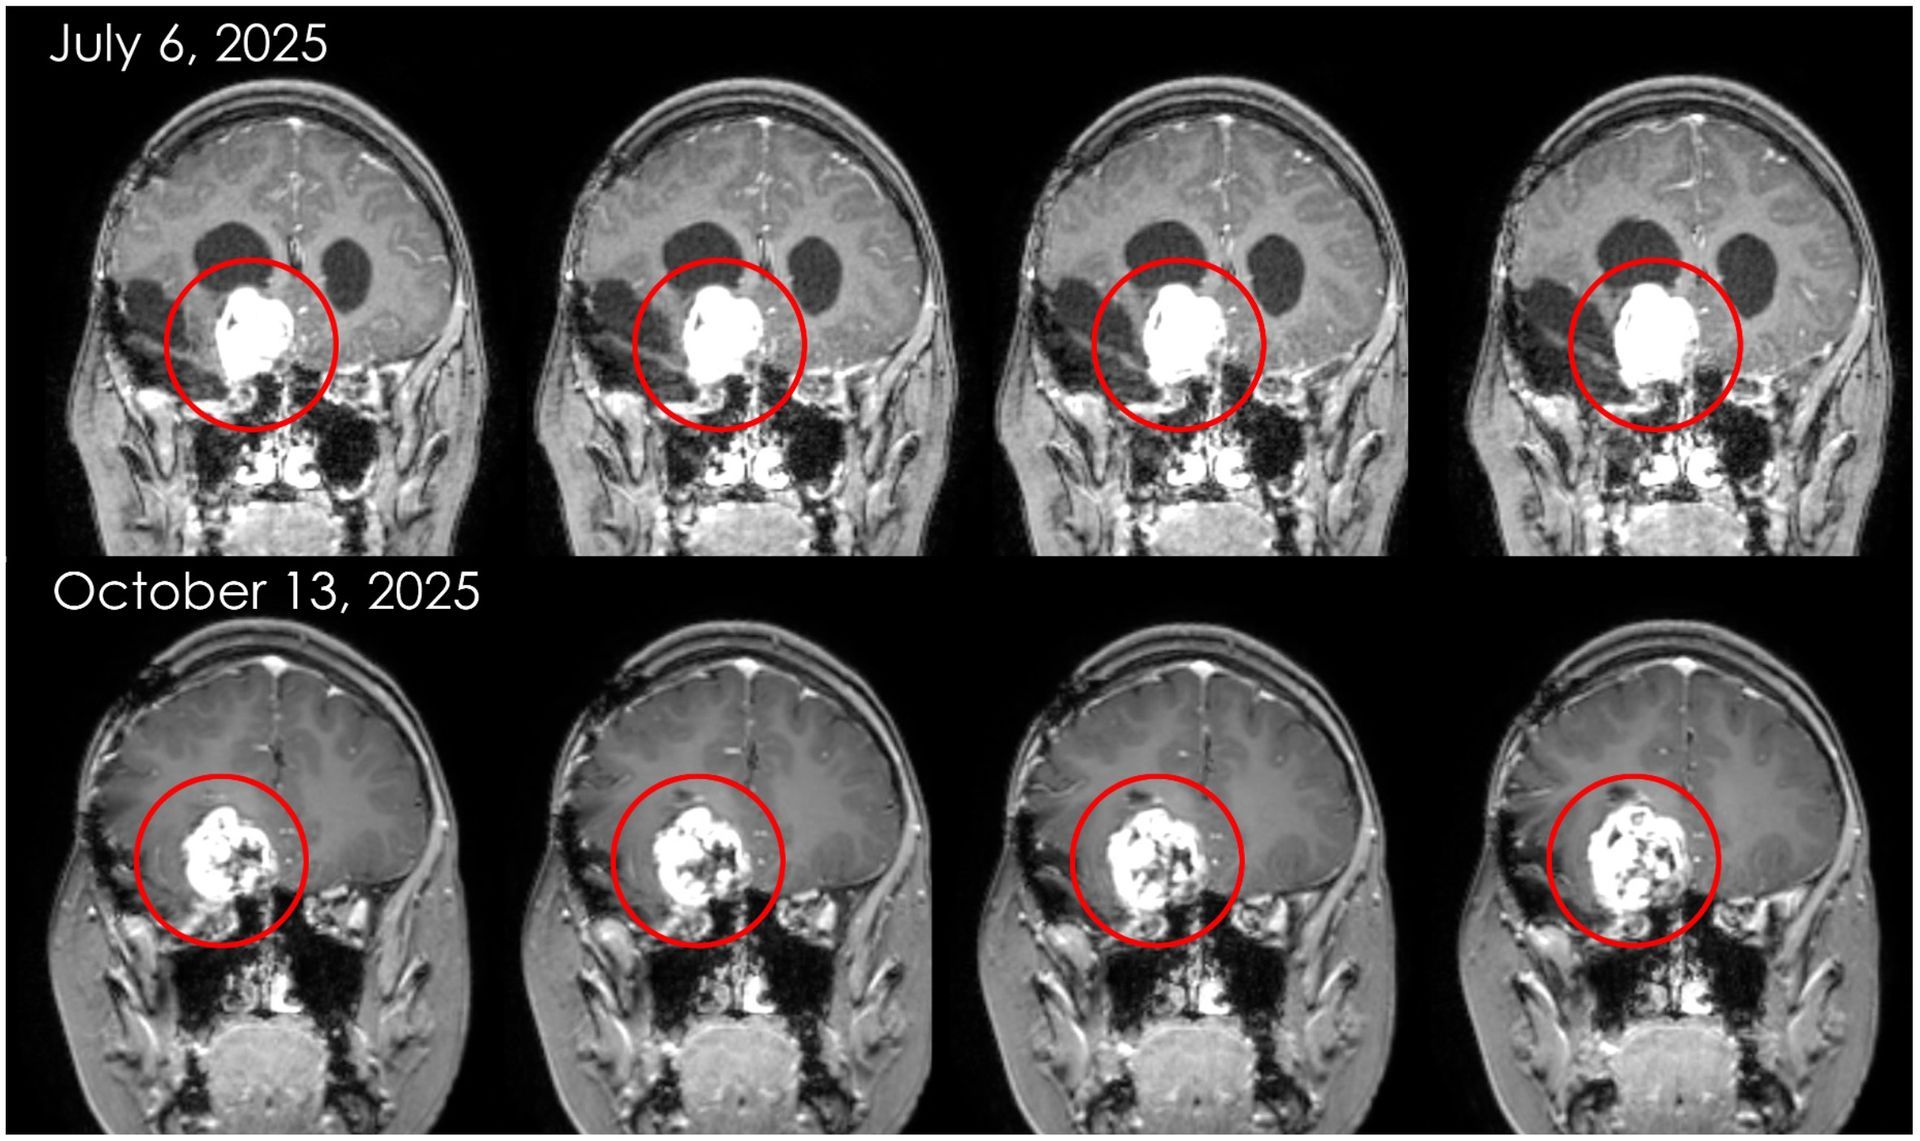

Sophie was the second patient, and first child, to ever receive NKore’s NK101 immunotherapy in December of 2023. She experienced no negative side effects, and her vision improved post-infusion. She received her second infusion in July of 2024 with no negative side effects and early signs of a positive clinical response.